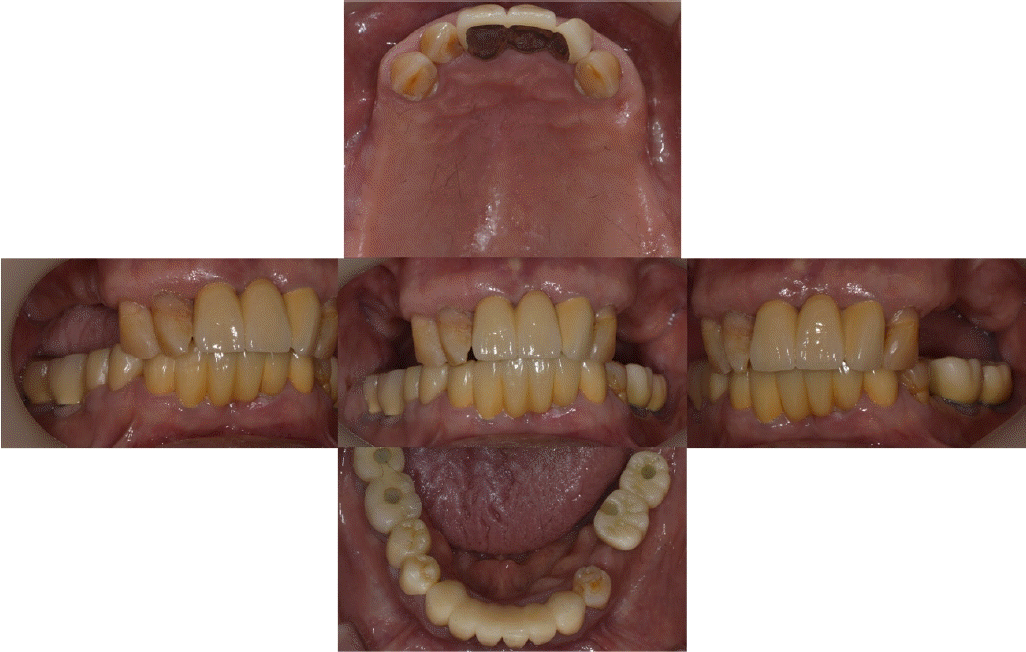

본 증례의 환자는 76세의 여성으로 상악 6전치만 잔존한 상태로 상악 가철성 국소의치의 제작을 위해 내원하였다. 상악은 6전치 중 상악 우측 견치와 좌측 견치의 상태는 동요도 및 파절 상태 없이 양호하였고, 상악 우측 측절치는 총생 상태였으며, 상악 우측 중절치와 상악 좌측 측절치를 이용해 3본 고정성 가공의치 형태로 상악 좌측 중절치의 수복이 되어 있는 상태였고, 상악 잔존 치조제의 상태는 중등도의 흡수 상태가 관찰되었다. 하악은 하악 좌측 제 2소구치는 잔존 치근 상태였다(Fig. 1). 상악의 경우엔 임시의치를 사용중이었고, 잔존 치근 상태인 하악 좌측 제 2소구치는 발거를 진행하였다. 전신병력으로는 B형 간염, 신장 투석, 파킨슨, 당뇨, 고혈압 및 협심증으로 다양한 약을 복용중이었고 비용 및 전신병력의 이유로 임플란트와 같은 수술적인 치료방법의 치료는 어려운 상태였다.상악은 양측 구치부의 결손이 있는 Kennedy Class I 으로 분류하고, 후방 결손부의 수복을 위해서 상악 가철성 국소의치의 제작을 진행하기로 결정하였다. 상악 가철성 국소의치의 디자인은 양측 상악 견치에 후방연장 국소의치의 유지를 위해 설면 레스트와 원심 유도면, 조직 언더컷으로 인해 RPA 클라스프를 설계하였고, 잔존 치아의 개수가 적어 주연결장치는 구개부를 대부분 피개하는 구개판형 연결장치를 설계하였다. 간접 유지의 역할을 위해 추가적인 설면 레스트의 부여를 고려하였으나 양측 측절치에 설면 레스트의 형성은 상악 우측 측절치의 총생 및 상악 좌측 측절치의 기존 보철 수복물로 인해 한계가 있었다(Fig. 2). 의치의 무게로 인한 탈락을 최대한 보완해보고자 금속 구조물의 제작을 코발트-크롬 합금보다는 보다 가벼운 특징을 가진 티타늄 합금(Ti-6Al-4V)을 이용하여 제작하기로 결정하였고, 7년 이내 요양급여를 통한 보험의치 적용을 받은 기록이 있어 비보험 진료로 진행하기로 하였다.해당 수복의 진행을 위해 양측 견치에 설면 레스트 시트를 구강 내 직접 형성 하였고 삽입 철거로를 고려하여 원심면의 치질 성형을 시행하였다(Fig. 2). 이후 개인 트레이를 제작 후 부가중합형 실리콘(Selection-K V.P.S, Shinhung Co., Seoul, Korea)를 이용해 기능인상채득을 시행하였다(Fig. 3). 이후 주모형을 제작하였고 제작된 주모형을 모델 스캐너(DOF Freedom HD, DOF Inc., Seoul, Korea)를 이용해 스캔하여 디지털 데이터를 형성하였다(Fig. 4). 이후 디지털 데이터를 이용하여 CAD 프로그램(3Shape dental system, 3Shape Inc., Copenhagen, Denmark)를 이용하여 금속 구조물을 디자인하였다(Fig. 5). 이후 해당 디자인된 금속 구조물을 선택적 레이저 용융 방식(SLM)의 3D 프린터(David 1.0, Merain Co., Incheon, Korea)를 이용하여 티타늄 합금(Ti-6Al-4V)으로 금속 구조물을 제작하였다. 또한 티타늄 합금과의 무게 비교를 코발트-크롬 재질의 금속 구조물도 티타늄 합금(Ti-6Al-4V)의 금속 구조물 제작에 사용한 동일한 CAD 파일을 이용하여 3D 프린팅을 통해 제작하였다.제작한 티타늄 합금(Ti-6Al-4V)과 코발트-크롬 합금의 금속 구조물의 후처리를 완료 후 주모형에 적합도 확인 및 무게 측정을 시행하였으며, 티타늄 합금(Ti-6Al-4V) 금속 구조물의 무게는 5.6g 이었고, 코발트-크롬 합금의 무게는 9.5g으로 티타늄 합금(Ti-6Al-4V)의 무게가 코발트-크롬 합금보다 41% 정도 더 가벼운 무게를 나타냈다(Fig. 6).제작된 티타늄 합금(Ti-6Al-4V) 금속 구조물의 적합을 환자 구강내에서 확인하였고, 이후 기록상을 제작하여 악간관계 기록을 채득 후 교합기에 부착하여 치아배열을 시행하였으며, 균일하게 중심교합 시 균일한 교합접촉을 이루는지 확인하였다(Fig. 7).